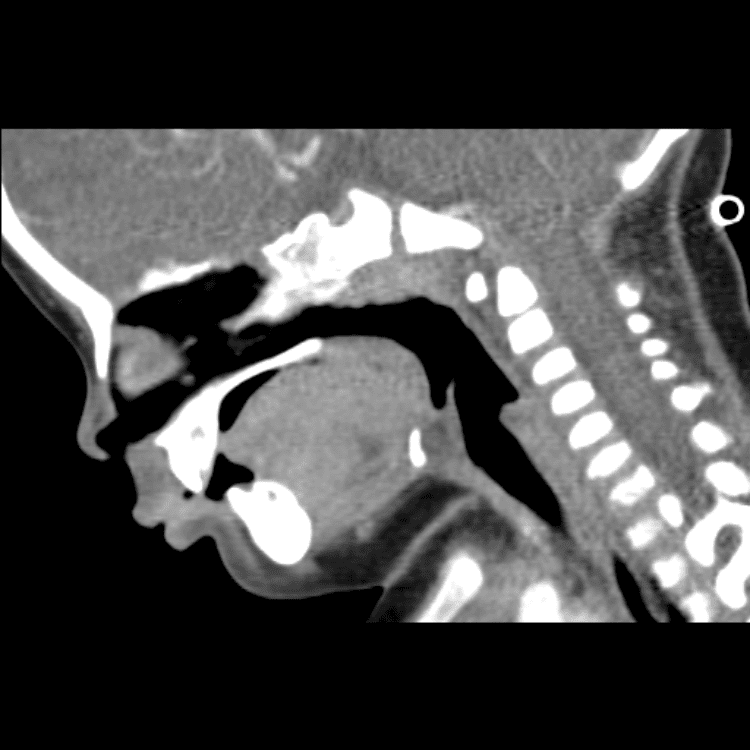

Head and Neck

Practice

Simulates call by including subtle or difficult cases and some normals.

27 cases